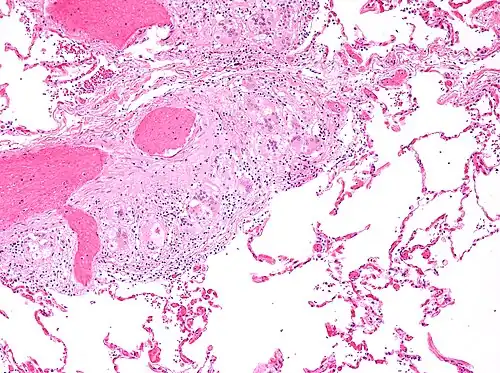

Asteroid body

An asteroid body is a microscopic finding seen within the giant cells of granulomas in diseases such as sarcoidosis and foreign-body giant cell reactions.[1]

There is controversy about their composition. Traditionally, they were thought to be cytoskeletal elements and to consist primarily of vimentin.[2] However, more recent research suggested that that was incorrect and that they may be composed of lipids arranged into bilayer membranes.[3]